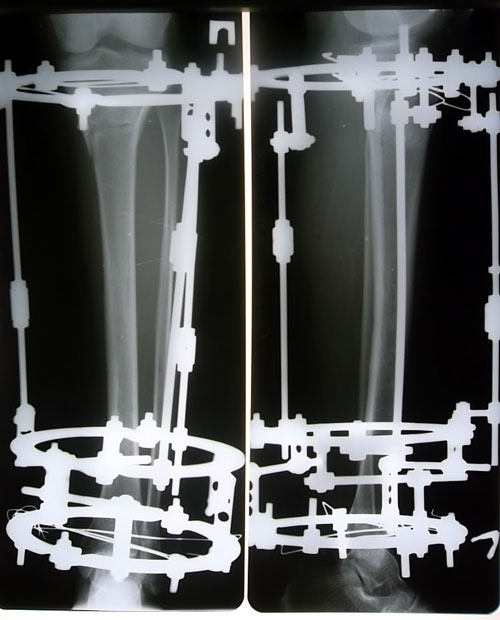

Рентген перед снятием аппаратов.

Сращение 100% - ое, отличная работа доктора!

Дата операции 10.04.2013г.

Дата снятия аппаратов 26.07.2013г.

Срок лечения 104 дня.